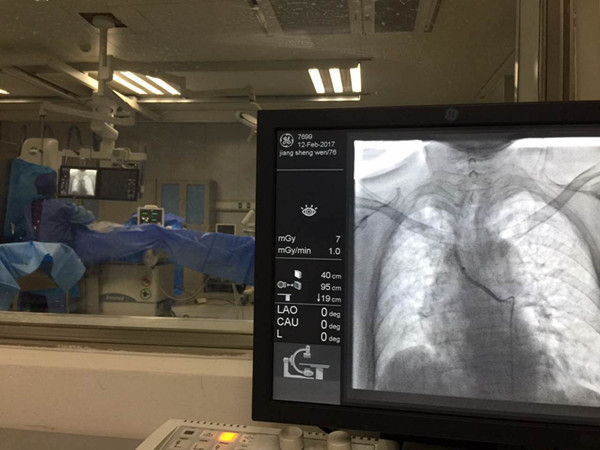

当天下午六点,耳鼻喉科接诊一例大咯血患者。患者五年前曾行喉全切、气管外置手术。来院时出现气管口喷射状咯血,短时间咯血量约100ml,初步考虑出血来源于气管、支气管。由于患者情况紧急,家属不了解此病并非由耳鼻喉科首诊。耳鼻喉科值医师接诊后,本着首诊负责制的原则,紧急吸除气管残余血液,保持呼吸道通畅,检测生命体征,静滴止血药等处理后患者出血暂时停止。之后迅速联系胸外、重症、呼吸等科室急会诊。但由于节假日无法行支气管镜检查寻找出血位置,求助多家医院后均被告知节假日无法检查及处理。患者夜间十二点再次大量咯血,耳鼻喉科值班医生紧急联系尚在家中的医学影像科介入室彭玉萍副教授商议行紧急介入治疗。彭教授接到电话毫不犹豫联系科室四名已熟睡的医护人员迅速来院。耳鼻喉科主治医师张滟,住院总夏翠,住院医师孙文艳即刻为患者完善术前准备。凌晨一点手术开始,彭教授与刘强主治医师主刀行支气管动脉栓塞,耳鼻喉科医师严密监测。手术过程中患者再次出现咯血,耳鼻喉科医师立刻对患者进行气管插管、吸血,保持呼吸道通畅。凌晨两点半介入手术结束,咯血基本得到控制,患者转危为安,转入重症监护室继续治疗。此次救治是多学科联合协作成功救治的又一次体现。